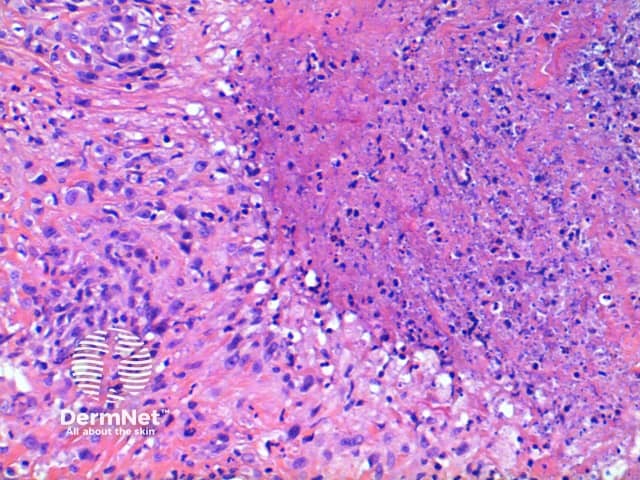

Figure 4

Rheumatoid nodule: The changes seen here are most similar to the subcutaneous variant of GA. Discriminating features seen in the rheumatoid nodule includes the presence of larger areas of eosinophilic necrobiosis, and a lack of mucin deposition. Clinical history is usually informative.

Epithelioid sarcoma: Always think twice when diagnosing GA on the digits. While the low power pattern may be similar due to the eosinophilic areas of necrosis, closer inspection will always reveal an atypical infiltrate. Immunohistochemistry is definitive in difficult lesions showing Epithelial membrane antigen (EMA) and Cytokeratin (CK) positivity.